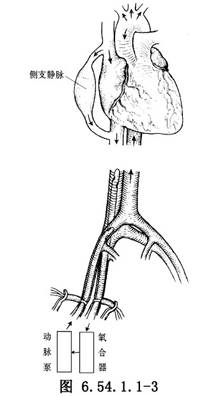

大腿稍外旋,自腹股沟韧带稍上方开始,沿股动、静脉走向,向远侧做10cm长纵行切口,解剖出股动、静脉并分别在其近、远侧绕阻断带暂时阻断血流。将股静脉横行剪开达周径之半(图6.54.1.1-1),插入有侧孔的F32~36号静脉导管,向近侧一直插入至下腔静脉,收紧阻断带,固定导管(图6.54.1.1-2)。并以适宜口径的导管做股动脉插管,导管尖端置于髂总动脉内。肝素化后开始部分转流(图6.54.1.1-3)。在流量仅达1000ml/min时病人情况即会明显改善,此时即可行全身麻醉气管插管。

2.胸部正中切口,劈开胸骨,显露心脏,按常规建立体外循环。阻断升主动脉行冠状动脉心脏停搏液灌注及心肌局部降温停搏。在已行部分转流的病人可不做主动脉及下腔静脉插管,仅作钳闭阻断主动脉和腔静脉以建立完全体外循环(图6.54.1.1-4)。